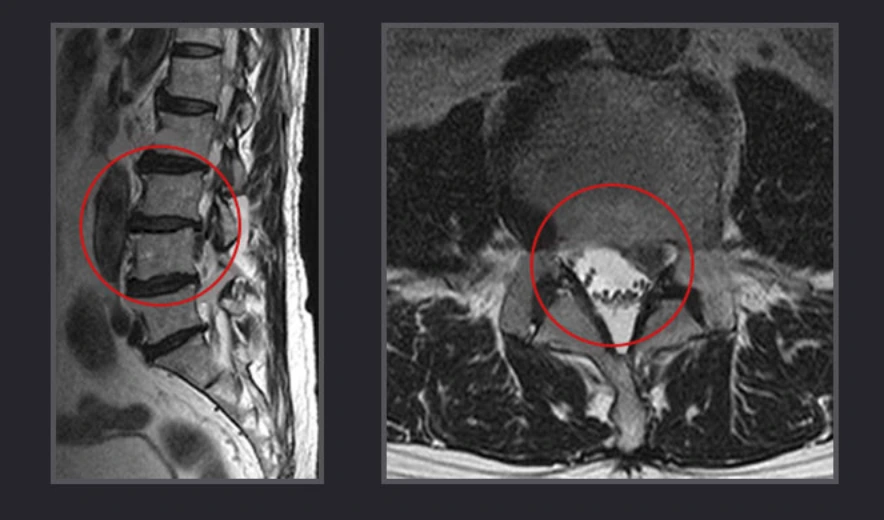

허리디스크는 외부의 충격, 잘못된 자세 등 여러 원인이 있지만 노화가 가장 큰 원인입니다. 노화로 인해 디스크를 감싸고 있는 섬유륜이 손상되어 디스크가 튀어나오거나 안의 수핵이 섬유륜을 찢고 나와서 인접한 신경을 누르기 때문이지요.

캡처.PNG

따라서 허리디스크가 진행되면 단순한 허리통증에서 그치는 것이 아니라 골반과 다리까지 저림증상이 나타납니다. 게다가 근력이 약해진 노년층에서는 잘못된 자세로도 디스크가 제자리에서 밀려 나올 수 있는 만큼 비수술적치료로 통증이 개선되지 않는다면 수술을 고려해야 합니다.